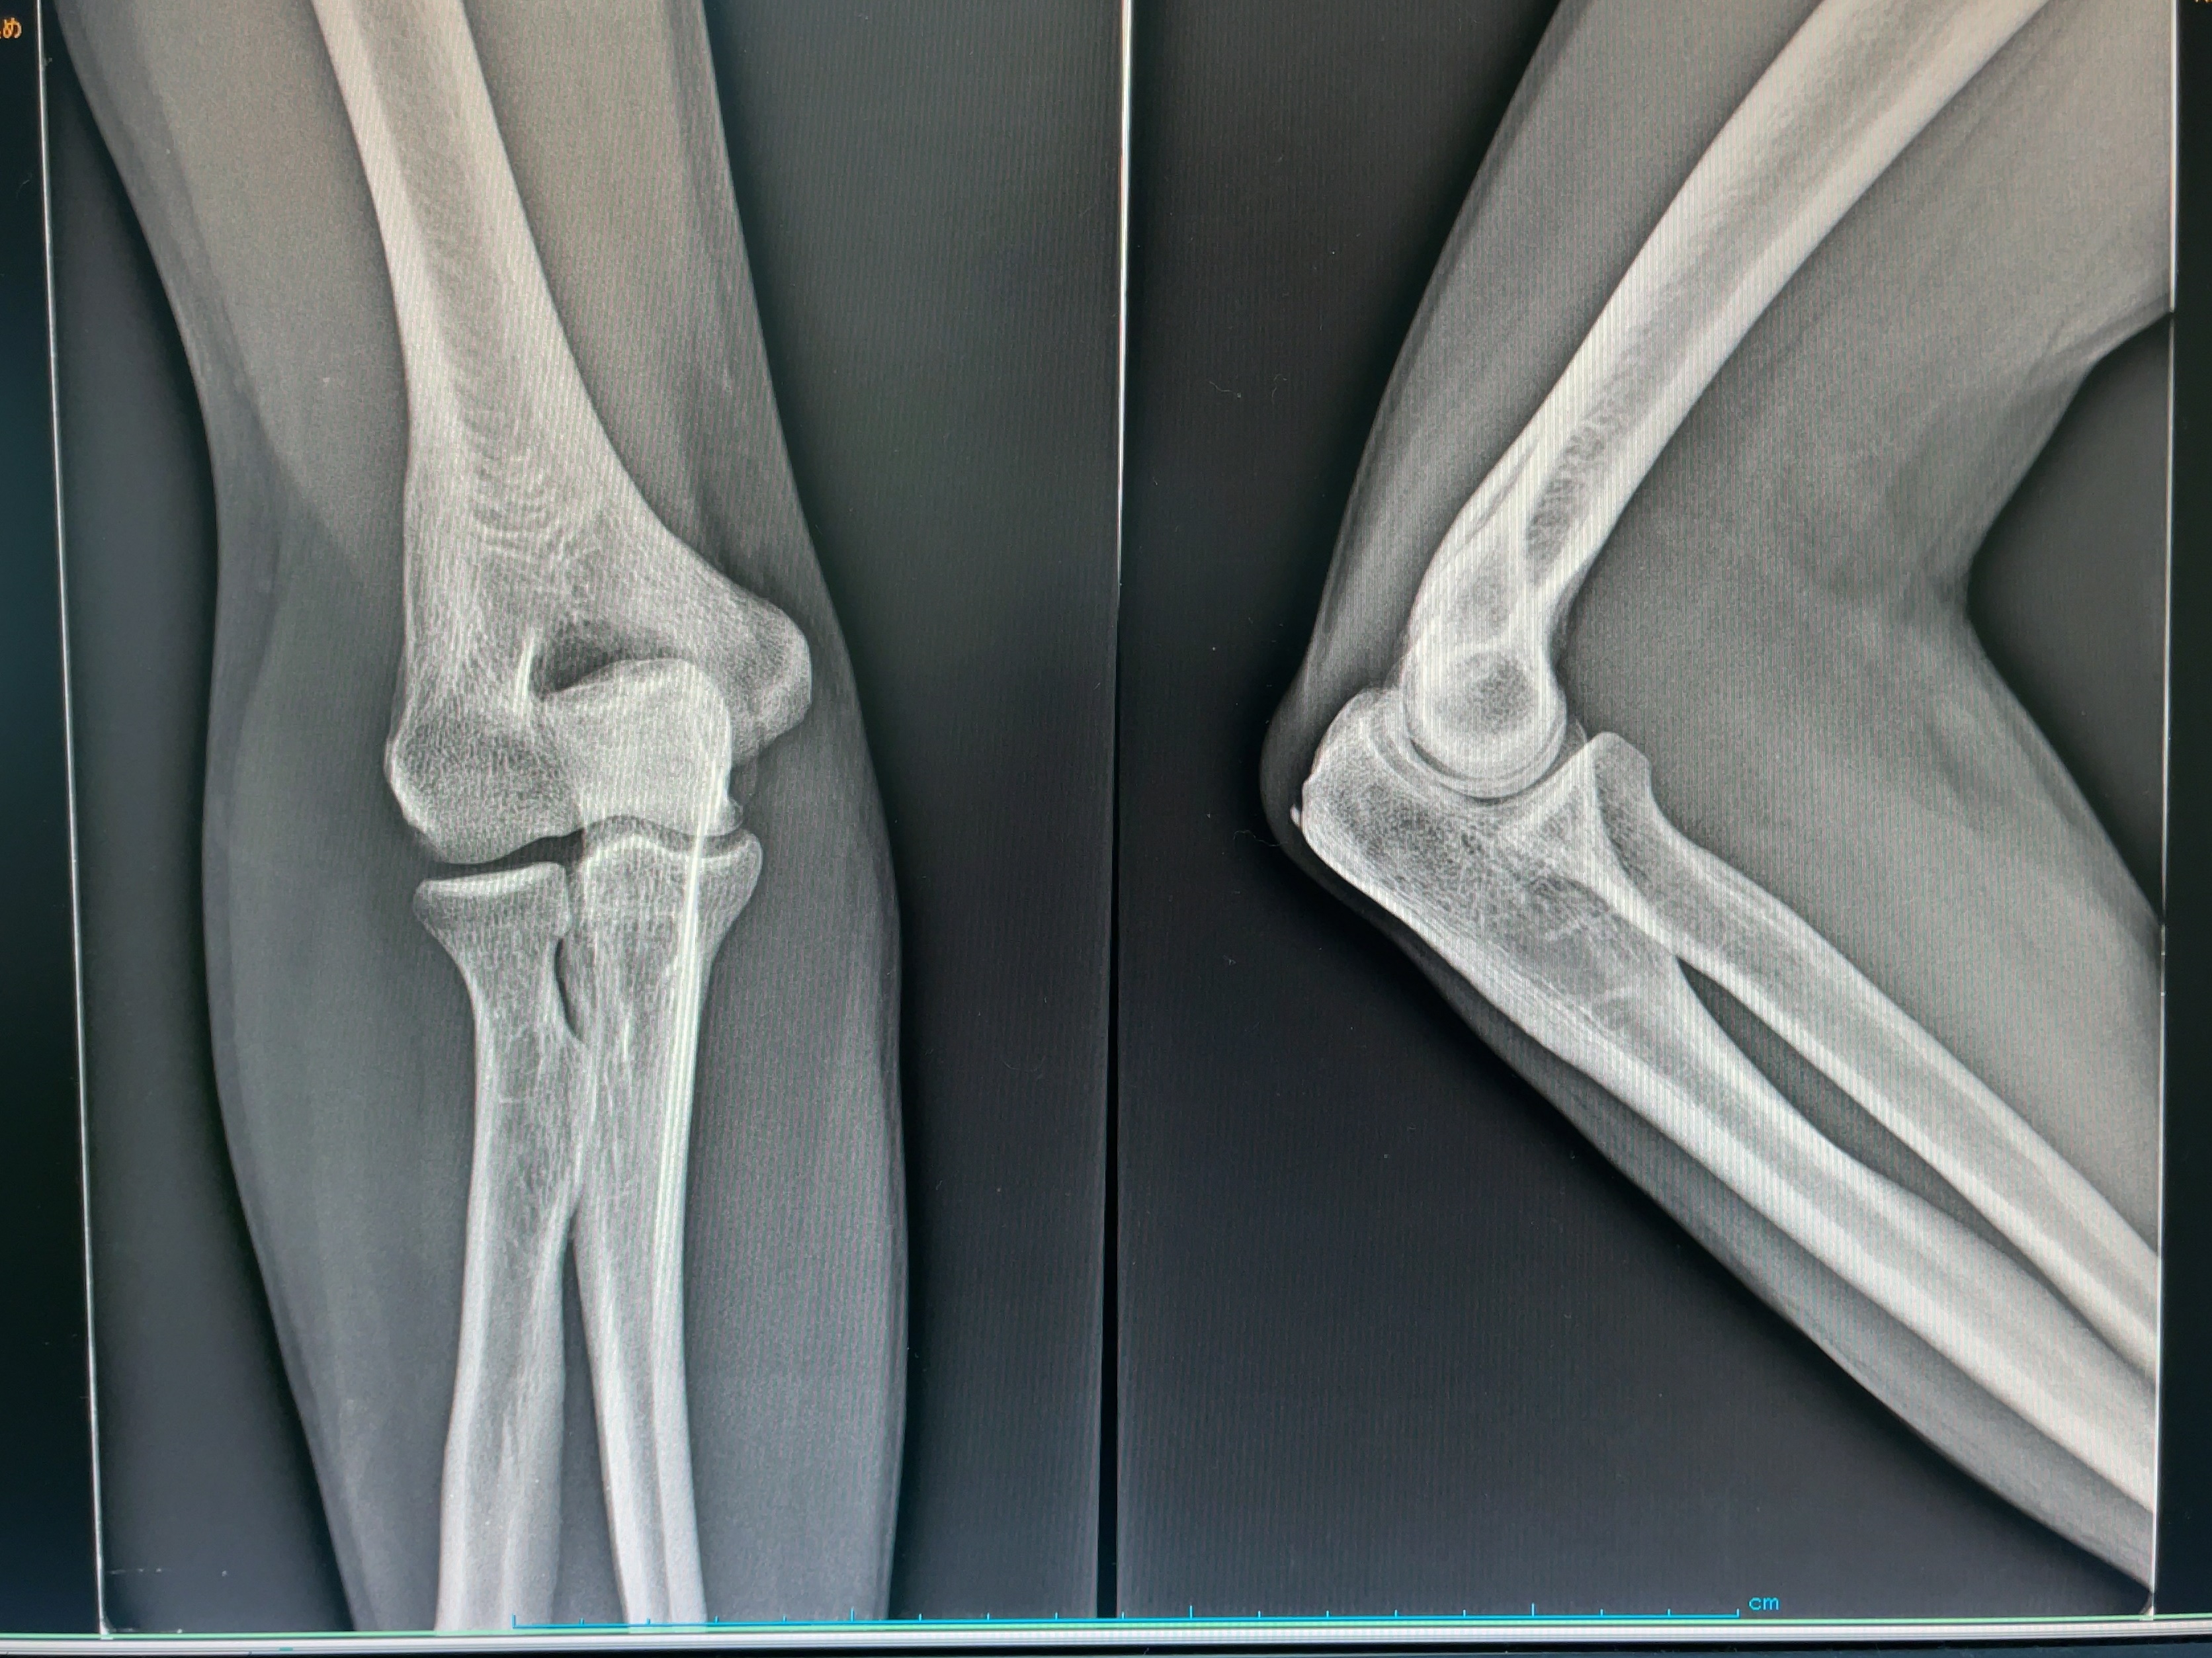

それはさておいて近所の整形外科に到着。X-ray、診察、電気治療、そして処方箋。電気って昔は非接触型だったけど、今は直接当ててびりびりというかぴくぴくするタイプなのね。初めて使った。まず定番のX線画像。

綺麗なものだが、肘の一部に石灰化がみられる、との所見。ただし今痛いところは石灰化が見られないので、炎症を抑えつつ電気治療にしましょう、ということに。電気治療は...

電極を2か所に。腹筋に貼るやつもこんな感じなのかな。その後処方箋をもらい薬局へ。フェルナビクスチック軟膏3%三笠、という塗り薬。三笠、が固有名詞なの?そして飲み薬はロルノキシカム錠4mgだ。胃に対して強い影響があるので副作用について注意を受ける。